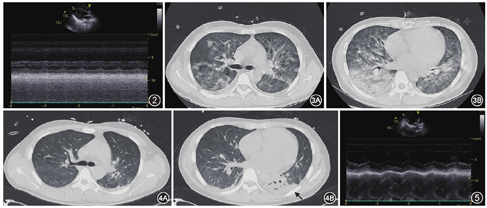

患者男,25岁,因"发热7 d,气促伴皮疹3 d"于2018年10月18日入院。入院前7 d无明显诱因出现发热,体温最高40.0 ℃,伴干咳,外院予头孢氨苄抗感染、退热处理后好转。入院前3 d再次发热,体温38.5 ℃,气促,活动后明显,伴全身乏力、肌肉酸痛、咳嗽、咳少许白黏痰,气促渐加重并出现端坐呼吸,结膜充血畏光,躯干及大腿遍布皮疹,遂急诊入我院。体检:体温37.6 ℃,心率108次/min,呼吸25次/min,血压94/58 mmHg[1 mmHg=0.133 kPa,去甲肾上腺素0.5 μg·kg-1·min-1],血氧饱和度(SpO2)80%(FiO2 41%)。急性面容,口唇黏膜局部破溃,结膜充血水肿,四肢湿冷,躯干及双侧大腿皮肤遍布斑丘疹,稍高于皮面,压之未见褪色,局部融合成片(图1)。颈静脉充盈,双肺大量湿性啰音。心音低钝,心率108次/min,律齐,各瓣膜听诊区未闻及杂音,腹软,无压痛、反跳痛,双下肢无水肿。辅助检查:血常规:白细胞26.1×109/L,中性粒细胞比值96.8%,血小板96×109/L。血生化:总胆红素21 μmol/L,谷丙转氨酶122 U/L,谷草转氨酶106 U/L,尿素氮7.4 mmol/L,肌酐128 μmol/L;肌钙蛋白I 26.37 μg/L;N端前脑钠肽28 100 ng/L;C反应蛋白(CRP)>200 mg/L;降钙素原2.31 μg/L;血沉(ESR)52 mm/1 h。血气分析(FiO2 41%):pH值7.238,动脉二氧化碳分压42.7 mmHg,动脉氧分压46.2 mmHg,乳酸3.8 mmol/L,碱剩余-8.5 mmol/L。心电图:窦性心动过速,T波低平(Ⅱ、Ⅲ、AVF、V4-V9)。心脏超声:房室大小正常,左室各壁收缩运动明显减弱,左室射血分数(LVEF)20%(图2)。胸部CT:双肺多发渗出性病变,近肺门处明显(图3)。初步诊断:(1)重症心肌炎、心源性休克;(2)肺部感染、Ⅰ型呼吸衰竭。为进一步治疗收住ICU病房。

入ICU后即予气管插管接呼吸机辅助呼吸,SpO2升至93%左右,予莫西沙星抗感染,利巴韦林+奥司他韦抗病毒,甲泼尼龙80 mg每日2次抗炎,丙种球蛋白20 g每日1次冲击,连续性床旁血液净化(CRRT),左西孟旦强心,红霉素眼膏保护结膜,辅以改善心肌代谢及营养支持等治疗。相关检查:自身免疫全套正常;痰培养、血培养未见细菌真菌生长;肺泡灌洗液检查未培养出细菌、真菌;血曲霉菌抗原及D-葡聚糖均阴性;麻疹病原学检查阴性;相关病毒(柯萨奇病毒、埃可病毒、腺病毒、EB病毒、巨细胞病毒、流感病毒、呼吸道合胞病毒、风疹病毒、单纯疱疹病毒)IgM均阴性;肺炎支原体(MP)IgM阳性(1∶320)。请皮肤科协助会诊考虑斯-琼综合征,继续目前治疗措施。治疗5 d后患者结膜充血水肿明显缓解,躯干及大腿皮疹颜色变淡,融合,循环稳定,停用去甲肾上腺素及丙种球蛋白,甲泼尼龙减量为40 mg每日1次。治疗第7天复查胸部CT:右肺病灶基本吸收,左肺下叶少许渗出性病变(图4);心脏超声:各房室腔大小及功能未见明显异常,LVEF 56%(图5);病情明显好转,予停甲泼尼龙,拔除气管插管。治疗第10天停用莫西沙星,治疗第14天各项生命体征平稳,结膜遗留少许充血,口唇黏膜恢复正常,躯干及大腿皮疹完全消退,康复出院。出院诊断:(1)重症心肌炎、心源性休克;(2)支原体肺炎(MPP)、Ⅰ型呼吸衰竭;(3)斯-琼综合征。